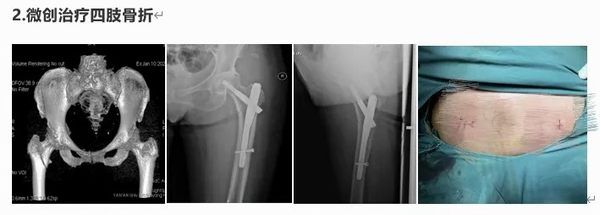

擅长四肢创伤骨折的微创修复,胸腰椎骨折复位内固定,髋关节置换术、断指(肢)再植,拇手指再造及四肢软组织缺损的显微外科。